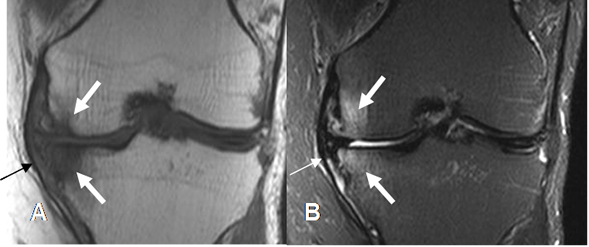

Fig 117 A. Trauma de rodilla.

A: RM coronal en T1 y B: RM coronal en STIR. Contusión en el compartimiento medial (Flechas gruesas), sin alteración en el LCM, el cual permanece intacto. (Flechas delgadas).